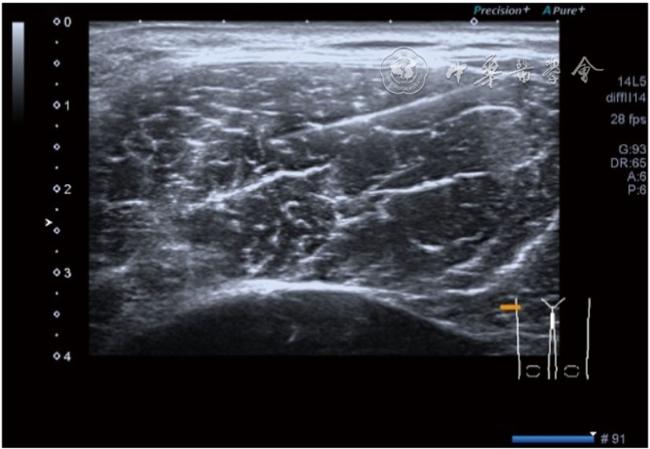

3.膝关节内局部治疗。随着病情发展,静态结构失衡,膝关节内部结构发生变化,会出现软骨损伤、脱落,关节间隙变窄,内外间隙不等,骨赘形成等。膝关节内局部治疗包括关节内症状性骨赘剥离、玻璃酸钠及PRP注射等。(1)膝关节内症状性骨赘针刀剥离松解治疗。由于软骨缺损或者力平衡失调,在关节内脱落软骨区会出现骨赘。部分骨赘引起疼痛,或者与髌骨撞击出现临床症状需要治疗。针刀剥离目的不是去除骨赘,而是剥离松解,缓解或者消除疼痛。以股骨外髁骨赘为例。患者平卧位,膝关节屈曲100°~120°。一般选用10 MHz超声探头,穿刺区域常规消毒,探头涂抹耦合剂后套入无菌手套碘伏消毒或使用无菌耦合剂。将探头置于患者皮肤表面,短轴扫查,显示关节面与骨赘,选用25G注射针,抽吸1%利多卡因3 ml于骨赘周围进行分层麻醉。选用直径1 mm的Ⅰ型2号针刀,在超声引导下从外侧向内侧到达骨赘,反复剥离,一般5~8刀后拔出针刀结束治疗(图18),局部压迫5分钟,无菌敷料覆盖。(2)膝关节髌上囊积液治疗。髌上囊积液在膝关节骨关节炎比较常见,尽管积液量可能很大,但通过软组织松解治疗后,大部分患者积液会减少或者消失。所以积液的治疗可以放在后面处理。超声引导下抽出积液,药物注射是常用的治疗方法。膝关节炎积液的治疗通常包括关节内皮质类固醇激素或者臭氧注射。如果慢性以滑膜丛型增生为主,针刀有限切割增生滑膜加药物注射可提高疗效。①髌上囊积液抽吸加臭氧注射治疗。患者平卧位,膝关节屈曲30°~60°,膝下垫一软枕。选用10 MHz超声探头,治疗前消毒准备同骨赘针刀剥离松解治疗。将探头置于患者皮肤表面,短轴扫查,找到积液最多处,应用22G针头,直接穿刺进入髌上囊抽出液体,然后根据髌上囊大小制备35 μg/L的15~20 ml臭氧注入髌上囊内拔出针头(图19),局部压迫2分钟,无菌敷料覆盖。②髌上囊慢性滑膜炎针刀切割松解治疗。患者平卧位,膝关节屈曲30°~60°,膝下垫一软枕。选用10 MHz超声探头,治疗前消毒准备同骨赘针刀剥离松解治疗。将探头置于患者皮肤表面,长轴或短轴扫查,找到积液最多处,用一次性5 ml注射器抽吸1%利多卡因3 ml于髌上囊进行分层注射麻醉,囊内也要注射适量麻药,尽量抽出积液。选用直径1 mm的Ⅰ型2号针刀,长轴扫查从近端向远端,短轴扫查从外侧向内侧,在超声引导下进入囊肿内对内壁及增生滑膜的不同方向、角度进行反复切割(图20),一般2~3分钟拔出针刀,然后囊内注射1%利多卡因3 ml+曲安奈德15 mg,结束治疗,局部压迫5分钟,无菌敷料覆盖。(3)膝关节腔PRP注射治疗。关节腔注射主要是为了修复软骨,如果不是为了治疗积液,不主张应用激素类药物。目前主要的注射药物为玻璃酸钠、PRP。按照传统的注射部位,多为髌上内、外或者髌下内、外注射点,但是超声不能观察到注射针的位置,药物也不能很好到达软骨损伤的部位,效果受到影响(图21)。膝关节软骨损伤的主要部位在髌股关节的股骨髁,超声可以很好地显示这一部位,并能显示软骨变薄。因此,由这个路径平面内进针注射,可以很好显示穿刺针的路径与位置。以注射PRP为例。患者平卧位,膝关节屈曲100°~120°,选用10 MHz超声探头,治疗前消毒准备同骨赘针刀剥离松解治疗。将探头置于患者皮肤表面,短轴扫查显示关节面,应用25G注射针头,抽吸1%利多卡因2 ml由内侧进针进行分层麻醉直达关节软骨面。制备4.5 ml PRP,直接注射到关节面,液体顺关节面分布,注射完毕拔出针头(图22)。局部压迫2分钟,无菌敷料覆盖。(4)髌骨软化超声影像融合技术下PRP注射治疗。髌骨软化是指髌骨关节面的软骨损伤,软骨下骨囊变,MRI能够明确诊断,但是超声不能显示。应用超声与MRI的影像融合技术,依据MRI明确注射部位,在超声引导下可将药物精准注射到软骨损伤的部位。患者平卧位,膝关节屈曲30°,下面垫一软枕。一般选用10 MHz超声探头,治疗前消毒准备同骨赘针刀剥离松解治疗。将MRI的原始图像数据导入超声设备中,进行手动影像融合,完全融合后,确定穿刺靶点,以MRI图像为目标,以超声图像为实时引导进行穿刺,到达目标后,注射提前制取的PRP 3 ml(图23),注射完毕拔出针头,局部压迫3分钟,创可贴覆盖。

图21 传统膝关节注射方法超声图像

图22 膝关节股骨髁关节面富血小板血浆注射治疗超声及操作图像